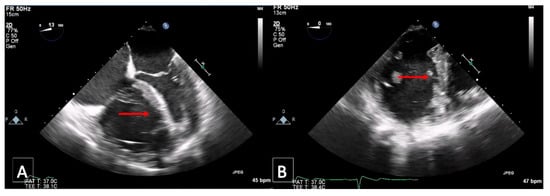

3.5. Transthoracic Echocardiography